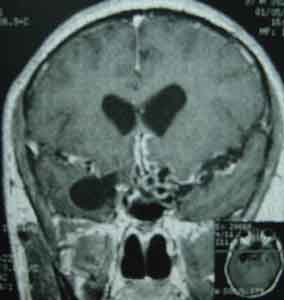

中樞神經系統感染2.中樞神經系統感染 EV71累及神經系統主要表現為無菌性腦膜炎、腦炎及癱瘓性疾病,多發生於5歲以下幼兒,1歲以下嬰兒發病率最高。臨床表現變化多樣,病情輕重不一,一般表現為陣攣、嘔吐、共濟失調、意向性震顫、眼球震顫及情感淡漠等。頭顱MRI及腦電圖檢查有助於明確疾病的嚴重性。